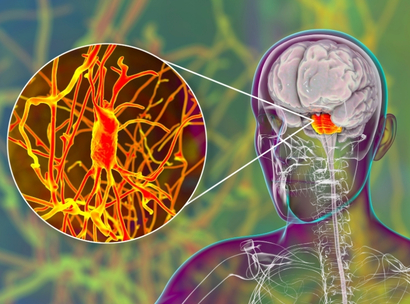

Central Nervous System

Medications affecting the brain and spinal cord, addressing disorders like epilepsy, sleep disturbances, and neurological imbalances.

Neurological Disorders

Specialized treatments for neurological conditions such as Parkinson’s, Alzheimer’s, and multiple sclerosis.